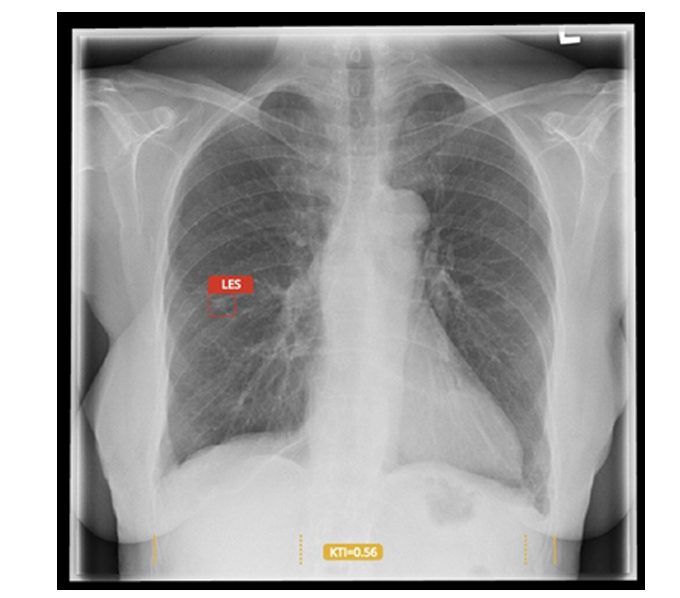

Carebot is software that uses artificial intelligence to automatically analyse X-ray images, supporting doctors in detecting findings, saving time, and increasing diagnostic confidence.